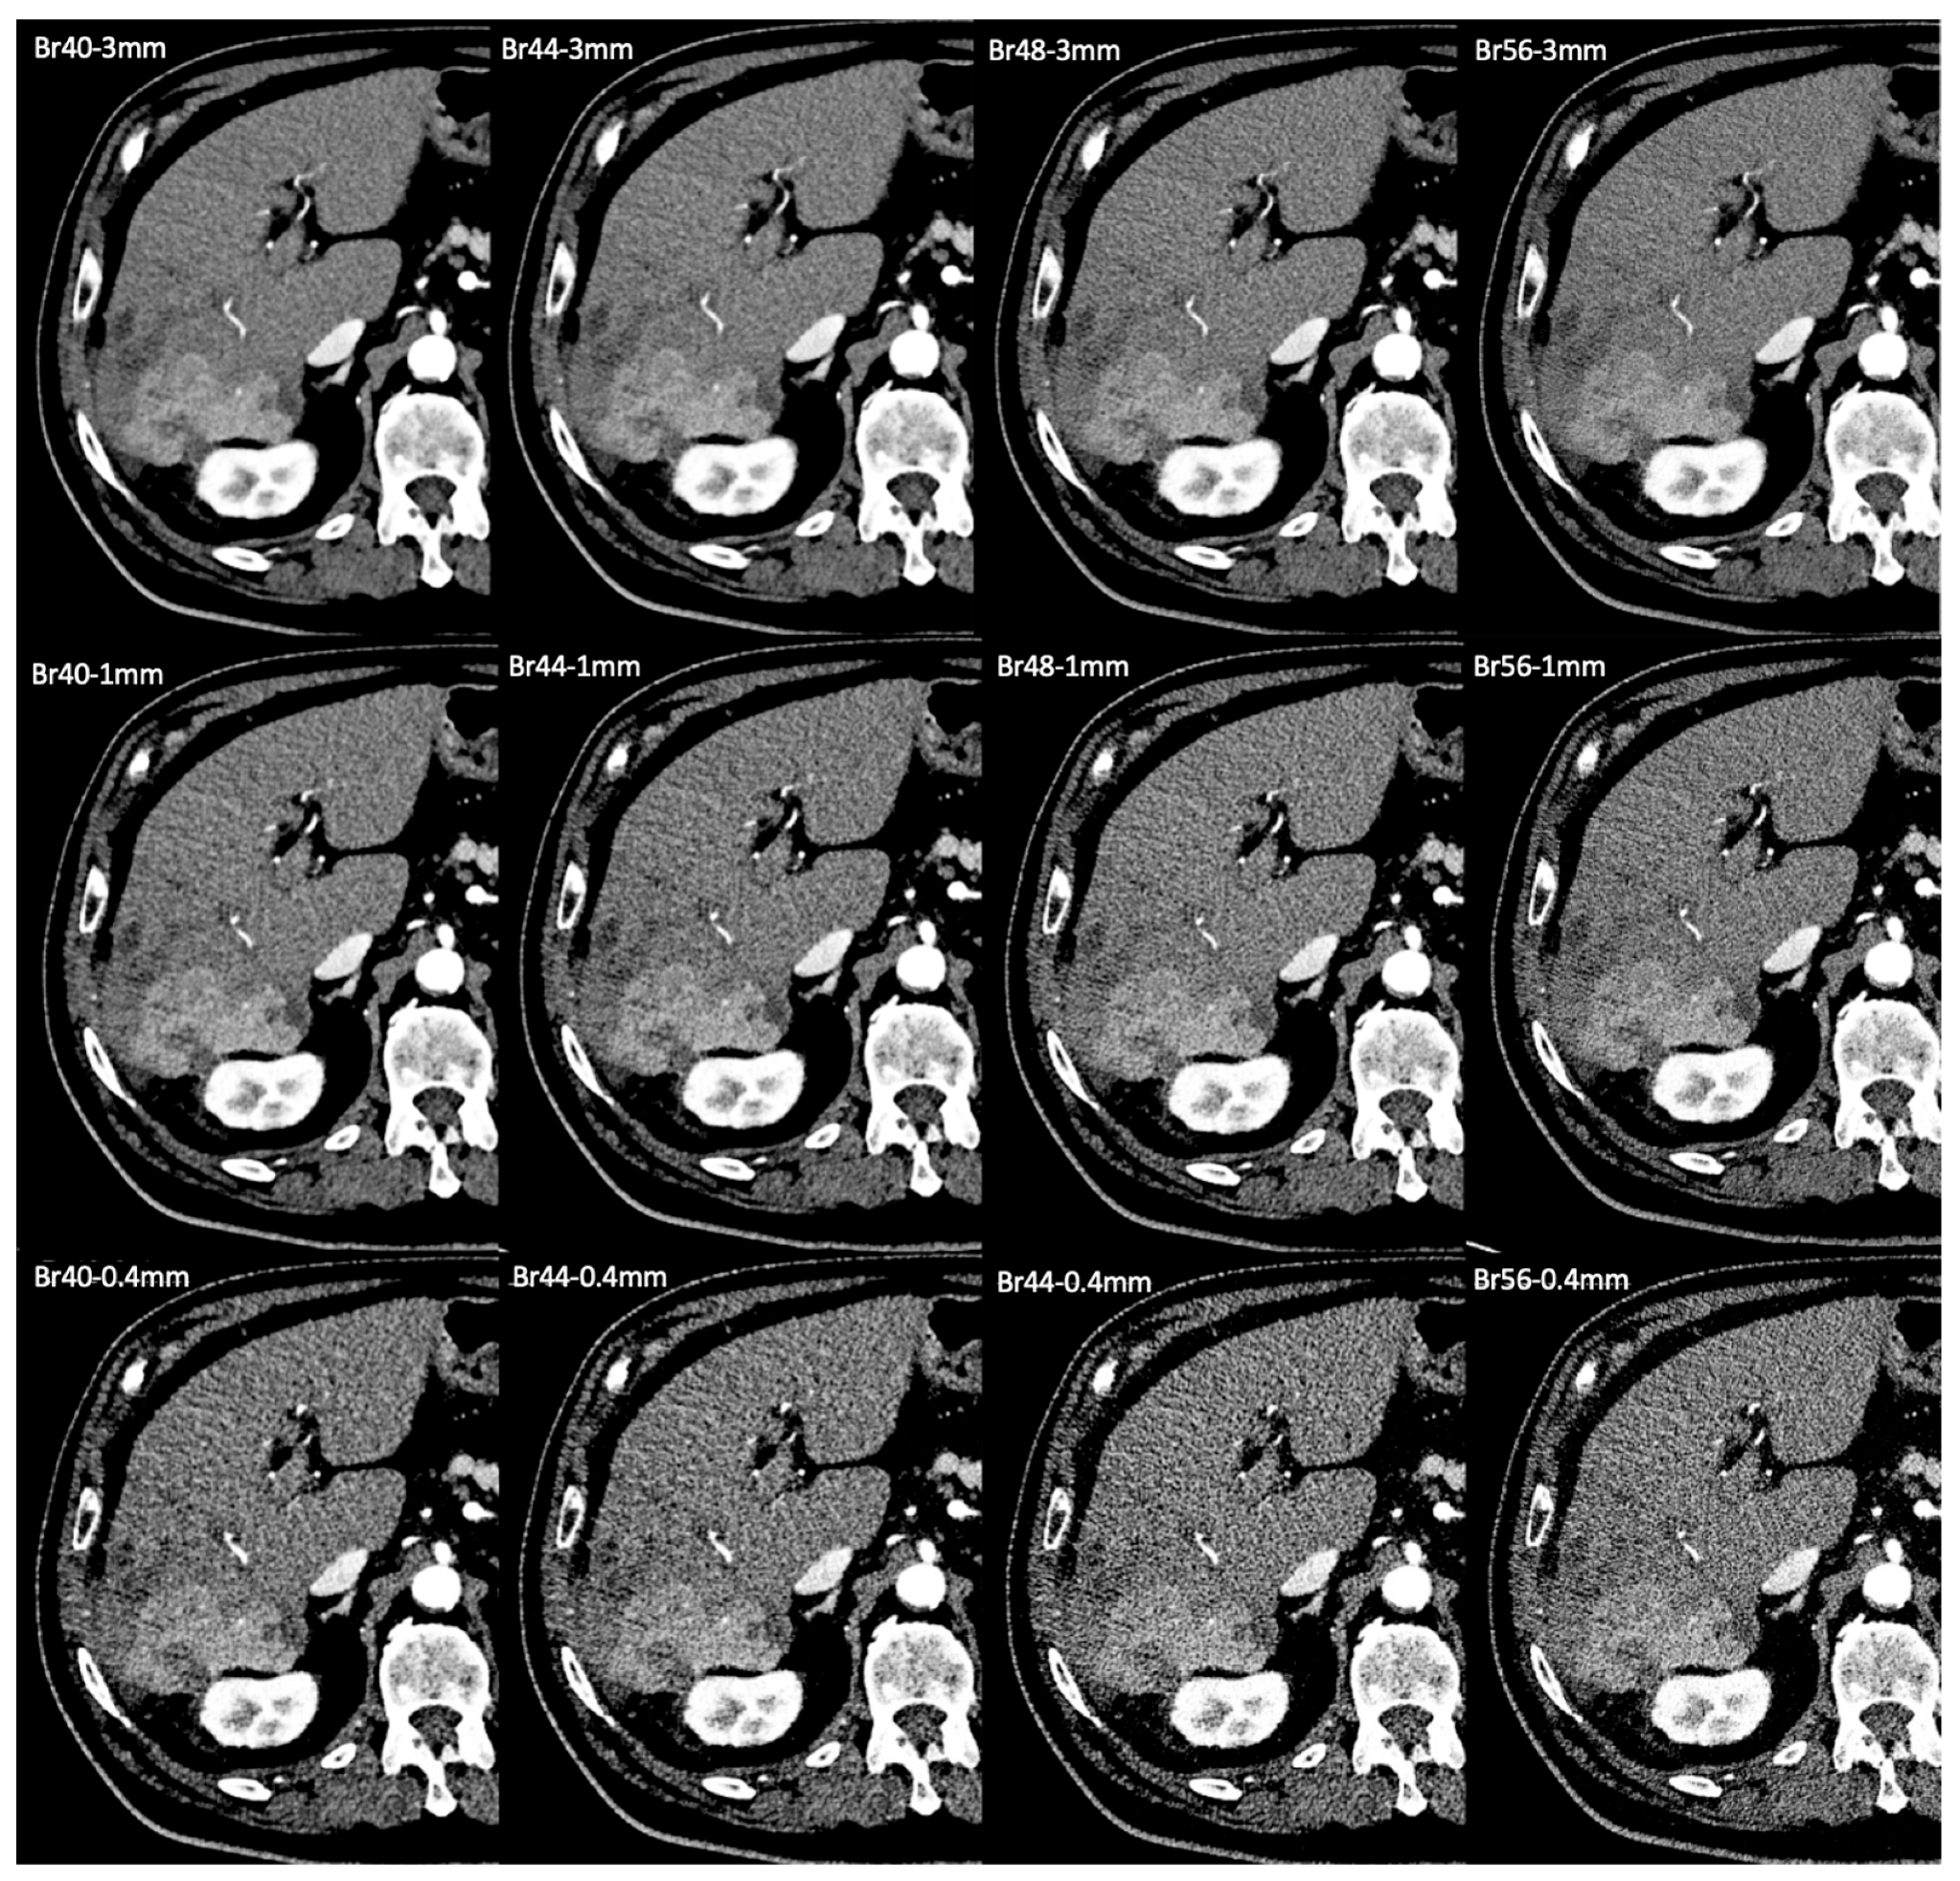

| Slice thickness | 3 mm/1 mm/0.4 mm |

| Kernel | Br40/Br44/Br48/Br56 |